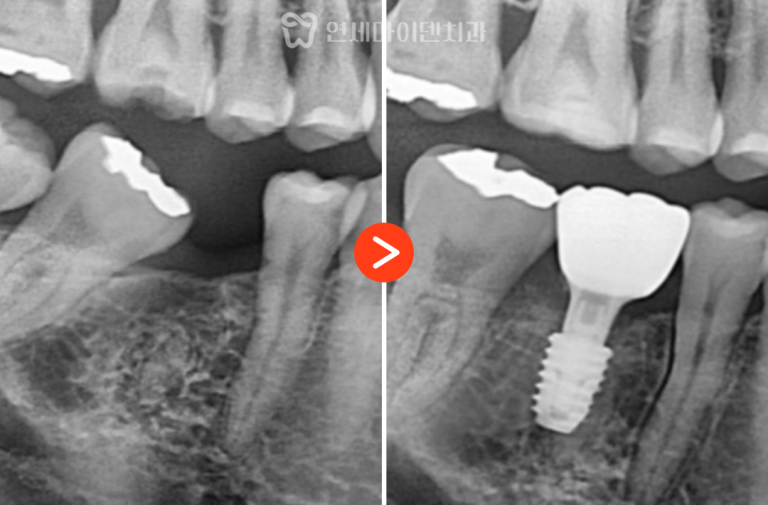

26번 치아 — 발치 즉시 임플란트

그러나 바로 뒤쪽의 #26번 치아는 상황이 달랐습니다.

수술은 뼈 보존을 고려해 즉시 식립 후

안정적으로 골유착을 유도하였고,

수술 부위의 잇몸도 건강하게 치유되었습니다.

3D 네비게이션 임플란트를 통해

임플란트 식립 위치를 계산하여

정밀하게 치료 계획을 세워줍니다.

발치 후 염증 조직을 깨끗하게 제거하고

계산된 위치에 임플란트를 식립하는

발치 즉시 임플란트를 시행하였습니다.

임플란트가 안정적으로 자리잡고

잇몸이 회복된 후에 2차 임플란트 수술을 진행합니다.

이후 최종 보철물도 구강구조에 맞게

자연스러운 형태로 제작해서 올려주었습니다.

치료 경과 및 예후

3년간의 추적 관찰 결과, #26번 임플란트는

주변 잇몸과 뼈의 안정성이 매우 양호한 상태로 유지되고 있습니다.